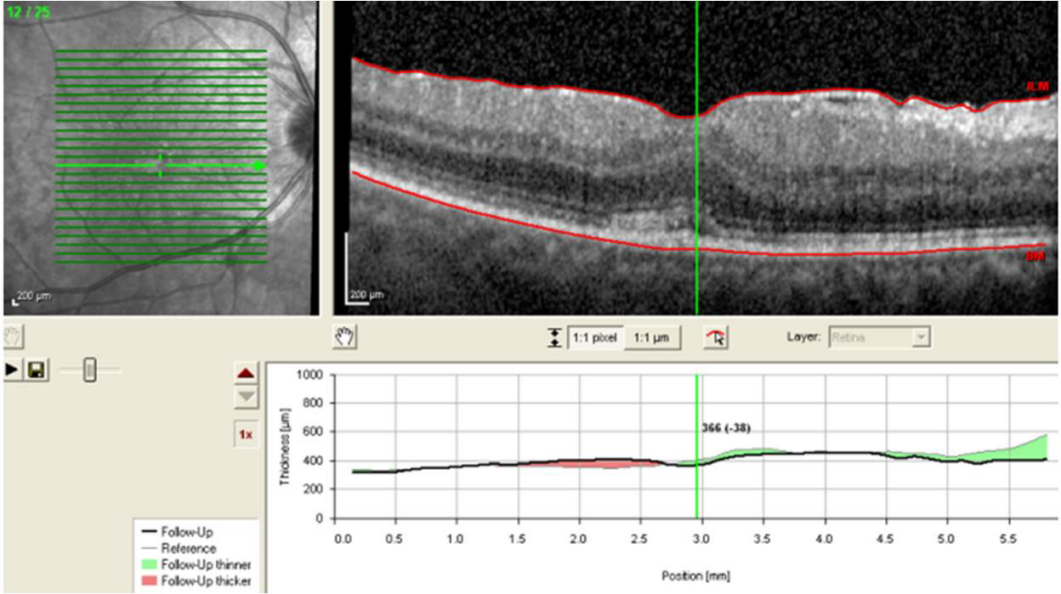

After the beginning of the cortico-antibiotic treatment there was a significant clinical improvement, as shown by the angiography images taken 2 months after the initiation of therapy (Figure 3 [Fig. 3]), as well as improvement of visual acuity bilaterally, with total recovery on the left eye. The visual acuity of 7/10 on the right eye can be justified by the further development of an epiretinal membrane (Figure 4 [Fig. 4]). From a neurological point of view, there was a full restoration of the deficits presented at the admission.

Figure 3: Retinography and angiography 2 months after the beginning of therapy (RE and LE)

Figure 4: Macular OCT of the right eye showing an epiretinal membrane